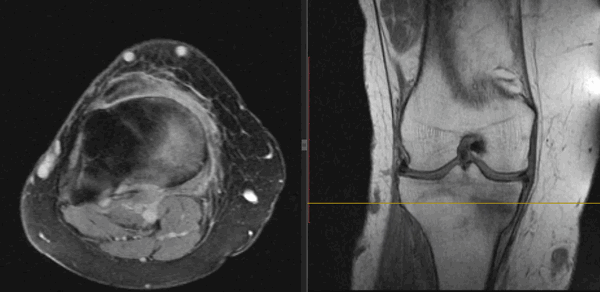

На Т2-ВИ в сагиттальной и корональной плоскостях определяется стресс-перелом дистальных отделов малоберцовой кости.

(Справа) При МРТ в сагиттальной плоскости в режиме STIR визуализируется изолированный перелом кубовидной кости, возникший вследствие избыточного отведения стопы. Следует отметить ступенеобразную деформацию суставной поверхности предплюсне-плюсневого сустава и ушиб сухожилия длинной малоберцовой мышцы.

4. МРТ при переломе кубовидной кости:

• Преимущества аналогичны КТ, однако МРТ позволяет обнаружить еще и отек костного мозга

• Используется для выявления стресс-переломов

• Позволяет оценить состояние сухожилия длинной малоберцовой мышцы:

о Проходит в одноименной борозде кубовидной кости, может повреждаться при переломе последней

(Справа) У футболиста при МРТ в аксиальной плоскости на ППВИ в режиме FS визуализируется изолированный оскольчатый перелом кубовидной кости. Следует отметить наличие вколоченного перелома суставной поверхности предплюсне-плюсневого сустава. (Слева) Пациент, получивший травму при падении с высоты. При КТ в аксиальной плоскости определяется продольно ориентированный перелом кубовидной кости, сочетающийся с компрессионным переломом пяточной кости. Вследствие перелома кубовидной кости наблюдается повреждение суставных поверхностей как пяточно-кубовидного сустава, так и сустава Лисфранка.

(Справа) У этого же пациента при КТ в коронарной плоскости визуализируются вертикально ориентированные переломы кубовидной и ладьевидной костей. Изолированные переломы кубовидной кости встречаются редко, чаще они сочетаются с переломами прочих костей стопы. (Слева) У конькобежца при МРТ в сагиттальной плоскости на Т1ВИ определяется стресс-перелом кубовидной кости. Типичным для такого типа перелома является наличие в кости множества трещин, расходящихся в стороны в виде звезды.

(Справа) У этого же пациента при МРТ в сагиттальной плоскости в режиме STIR большую часть кубовидной кости занимает обширная зона отека костного мозга. На фоне отека хорошо видны линии перелома.